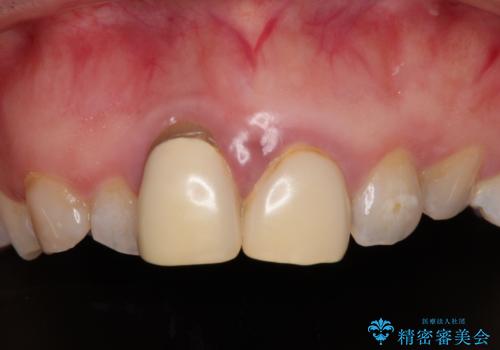

前歯のクラウンは変色が顕著なため、矯正治療後にオールセラミッククラウンによる補綴治療を行うこととしました。

前歯のクラウンは、歯肉内深くに削り込まれており、歯肉の炎症が継続していたため、矯正治療後に歯周外科処置を行い、歯肉の腫れを改善させました。